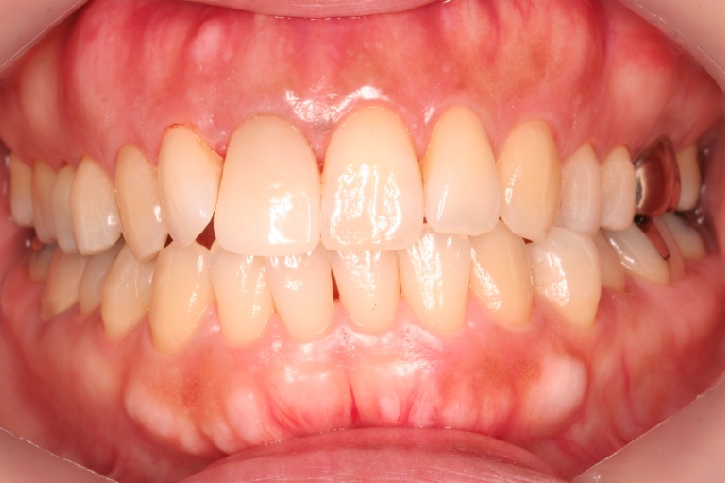

オールセラミックス修復

担当歯科医師:川津良介

2013年5月3日H.25.05.01 千葉市中央区 H.H様 左下7番 オールセラミッククラウン修復